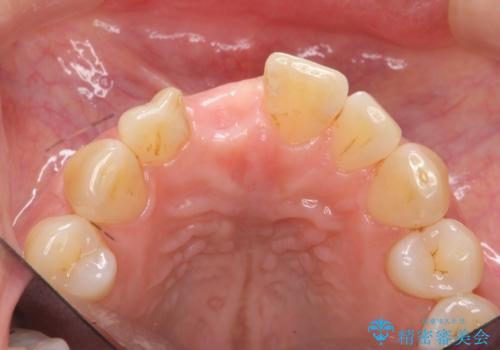

前歯 インプラントによる欠損補綴

- 目立つ一番前の歯を失い、接着剤で応急処置をしていましたが永続性のある修復を希望され来院されました。

入れ歯・ブリッジ・インプラントによる欠損補綴の方法のうち審美的で取り外しがなく隣の歯を削らない治療を望まれたため、インプラントによる審美・機能回復治療を計画します。

前歯のインプラント治療は適切に行えば、ブリッジのように隣の歯を削らずに審美的で機能的な状態に仕上げることが可能です。

インプラント周囲に十分な骨や歯ぐきの厚みの整備を行うことで、審美的なインプラントの仕上がりを達成することができます。